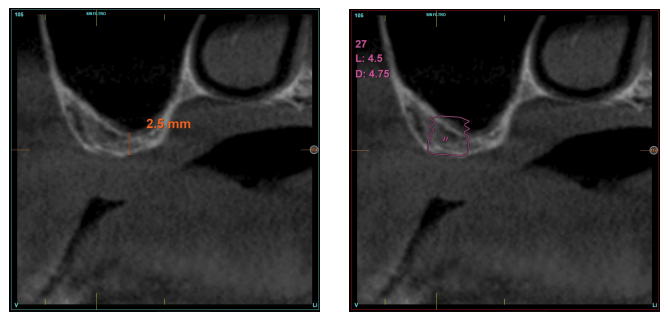

Fueron reclutados diez pacientes que cumplieron los criterios de inclusión, en los que fueron insertados 20 implantes. Tres de ellos fueron mujeres y la edad media fue de 72 (+/- 6 años). Ninguno de los pacientes era fumador en el momento de la cirugía y no presentaban enfermedad periodontal activa. El diámetro mayoritario de los implantes incluidos en el estudio fue de 5 mm (60%), seguido de 4,5, 5,5 y 4,75 mm (13,33% cada uno de ellos). La longitud predominante fue la de 5,5 mm (86,6% de los casos), siendo el 13,4% restante implantes de 4,5 mm de longitud. Las posiciones más habituales fueron para los segundos molares (molares 27 y 17) representando un 55% de los casos.

La altura media del volumen óseo residual fue de 3,1 mm (+/- 0,3 mm con un rango de 3-4 mm). En todos los casos se realizó una elevación de seno transcrestal, con hueso autólogo particulado obtenido del fresado de la zona de generación del neoalveolo para la inserción del implante, siendo la media de esta elevación sobre el ápice del implante en milímetros de 2,8 mm (+/- 0,99 rango 1,9 -5 mm). En el TAC de control al año de carga de los implantes estudiados, se mantiene la ganancia ósea lograda, no observándose disminución del volumen ganado, únicamente tres casos mostraron una disminución de entre 0,4 y 0,5 mm del volumen inicial al final (Tabla).

En las Figuras 2- 19 se muestra uno de los casos incluidos en el estudio.

la oseointegración del implante 6 meses después de la cirugía. Se observa una ganancia ósea de 4 mm.

en altura de 3,4 mm, siendo más uniforme en esta ocasión en toda la zona de la cresta. Se planifica un implante de 4,5 mm de longitud y

4,75 mm de diámetro.